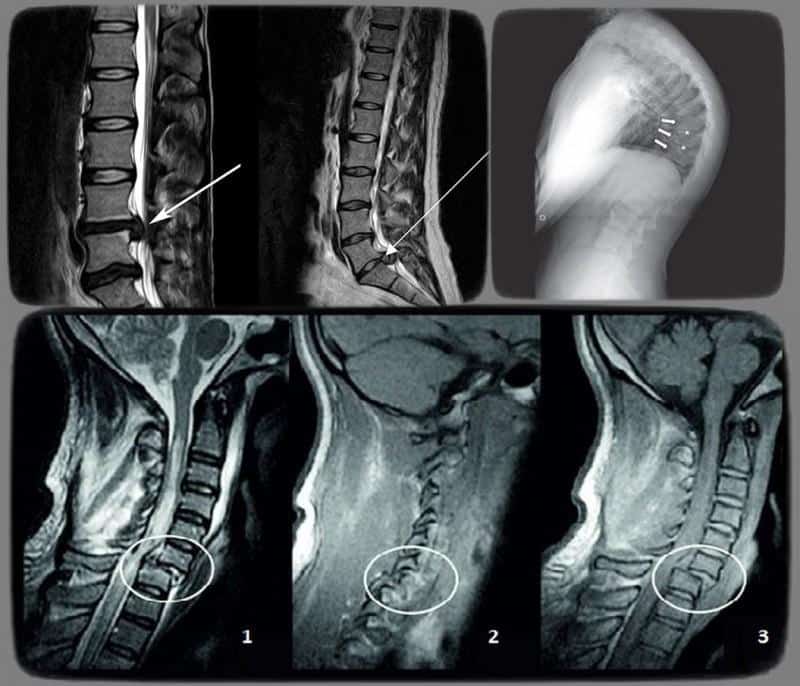

Затем проводятся лабораторные исследования, такие как общий анализ крови и мочи, а также аппаратные методы диагностики, включая рентгенографию, компьютерную томографию (КТ) и магнитно-резонансную томографию (МРТ).

Справка. Наиболее информативным методом в данной ситуации считается МРТ, так как оно позволяет детально оценить состояние всех тканей и структур.

В ходе этого обследования могут быть выявлены следующие МР-признаки нарушений статики пояснично-крестцового отдела позвоночника или других его сегментов:

- состояние межпозвонковых дисков;

- наличие межпозвонковых грыж;

- степень и направление смещения межпозвонковых дисков;

- аномалии развития позвоночника;

- характер и выраженность искривления позвоночного столба;

- состояние спинного мозга;

- скорость движения и давление спинномозговой жидкости;

- поражение нервной ткани;

- нарушения кровообращения;

- степень патологических изменений в костных структурах.

Кроме того, данная методика позволяет выявлять травматические, воспалительные, инфекционные и дистрофические процессы в тканях.